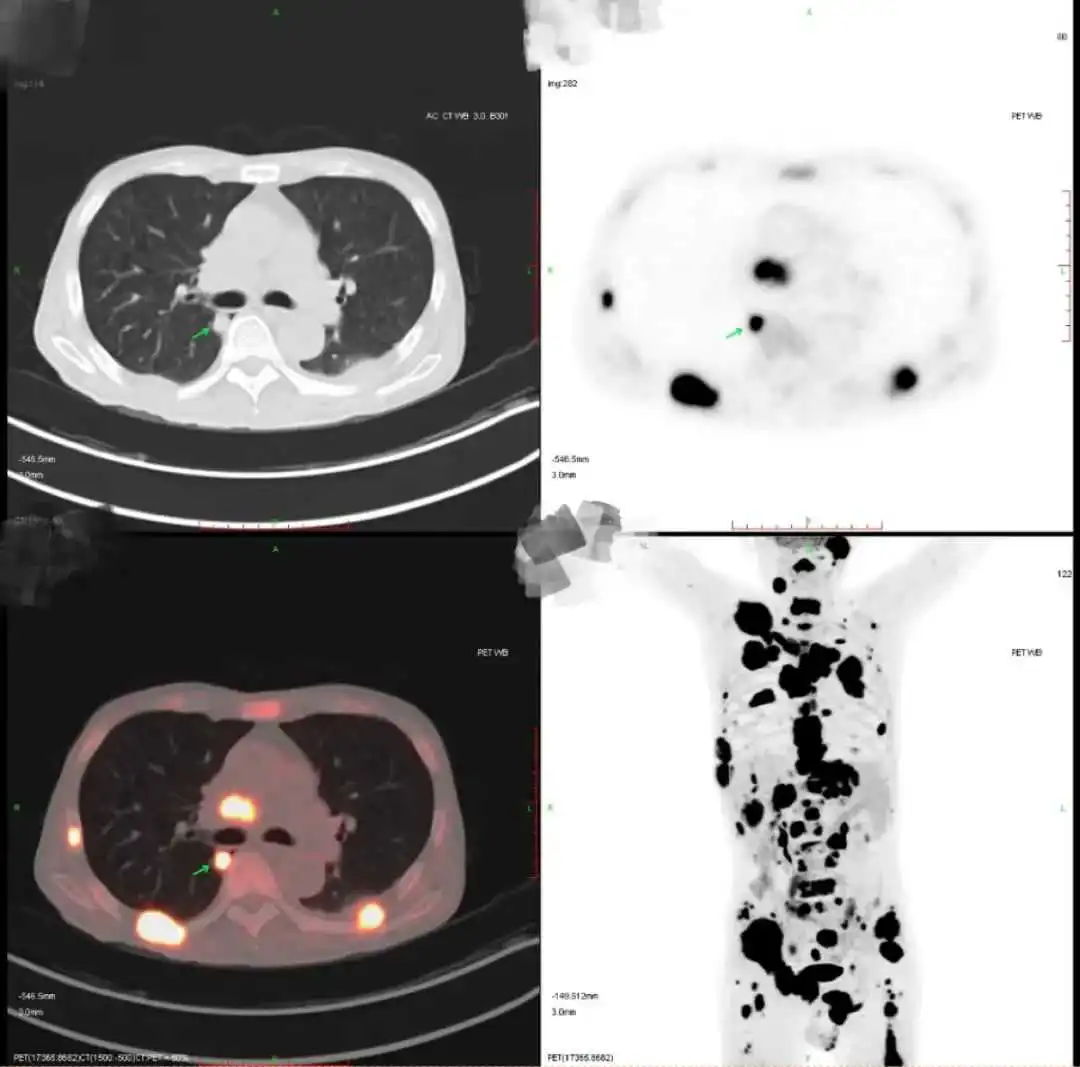

结果显示,闫先生病灶中的癌细胞很可能起源自肺部。

(PET-CT提示右肺上叶恶性病变可能,

且伴有全身多发转移)

孙旭迅速为他安排了PET-CT,结果在右肺上叶发现了一个小于1公分的病灶。

谜团解开了,闫先生确诊为肺癌晚期,且伴有多处转移。医生们的努力终于找到了真凶,这起“悬案”就此告破!